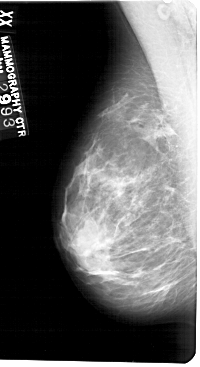

A_1546_1.LEFT_MLO

LEFT_MLO LINES 5491 PIXELS_PER_LINE 2986 BITS_PER_PIXEL 12 RESOLUTION 43.5 NON_OVERLAY